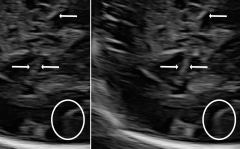

Three in vivo Bmode fetal images with and without aberration correction are presented in Figs. 10-12. GIF images of examples A-L (see Fig. 9 and Table 5) alternating between the corrected and uncorrected images are uploaded as supplementary material. The differences in image quality are easier to appreciate in the GIFs than in a side-by-side comparison. The data points for the three examples are colored black in Fig. 9. Table 5 give tabular values for the global sound speed estimate, sharpness increase (κ𝜅\kappa) and answers from the clinical evaluations.

Figure 10: Example A. In vivo fetal Bmode image using constant 1540 m/stimes1540dividemetersecond1540\text{\,}\mathrm{m}\text{/}\mathrm{s} and the estimated average sound speed map. The average sound speed map is shown in the top right corner and the rightmost colorbar indicates the sound speed values. Alternating GIFs are found in the supplementary material.

The in vivo examples A-C, in Figs. 10-12 respectively, show different nuances of how sound speed aberration correction improves focusing quality. A noticeable improvement in Fig. 10 is the improved contrast and clarity of borders. The sound speed correction seems to remove the double structure indicated by the arrows in Figs. 10c-10d. The skull border and the brain structures in Fig. 11 are also better defined and clearer after aberration correction. Example C in Fig. 12 is the image with the highest increase in Tenengrad κ𝜅\kappa, seen from Fig. 9 and Table 5. The improvement in image quality is evident around the boundary of the fetus body and the correction sharpens the structures indicated by the arrows. The improved contrast between the layers in the shallow tissue layers is also noticeable.